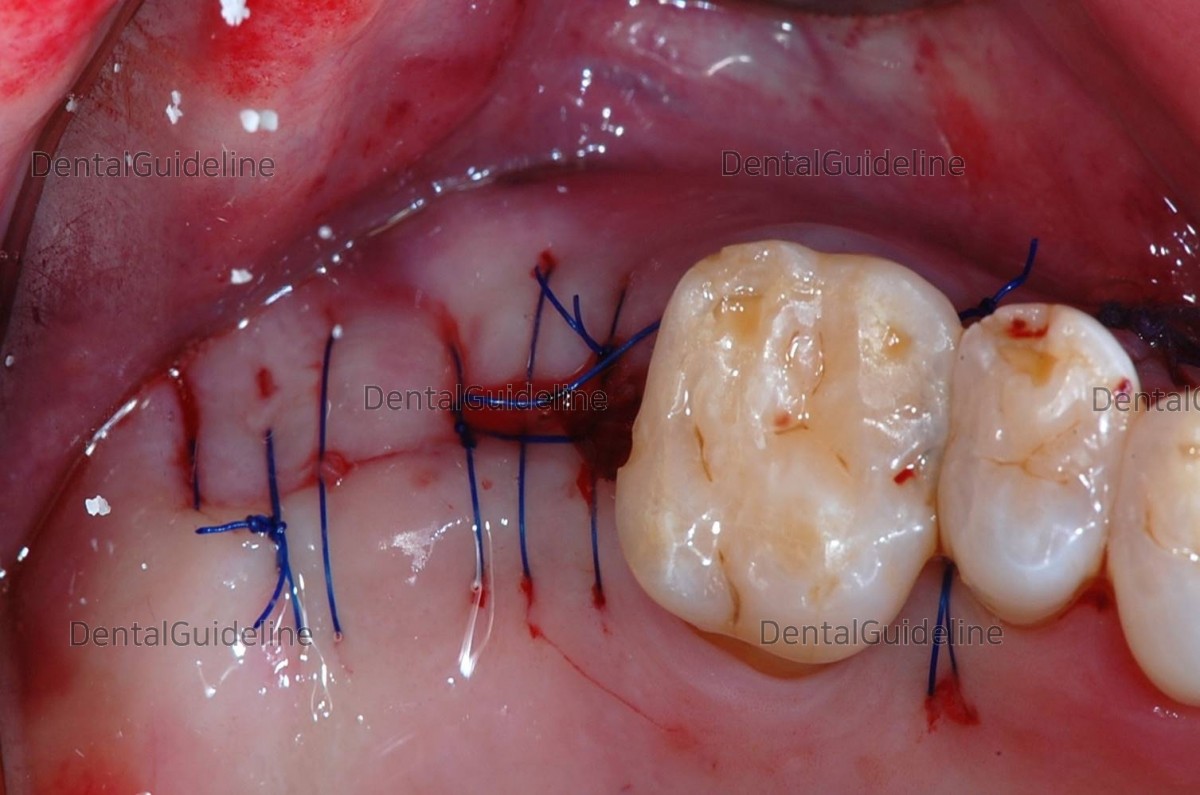

Suture